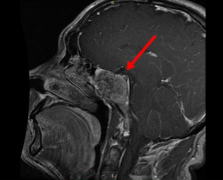

脊索瘤 是一种起源于胚胎脊索残余的局部侵袭性肿瘤。使用监测、流行病学和较终结果数据库的基于人群的研究表明,每106人脊索瘤发病率为8.4。尽管斜坡脊索瘤占全部脊索瘤的三分之...

颅内脊索瘤如何治疗?颅内脊索瘤就是指发生在脑内的颅内脊索瘤,是颅内少见的的一种损害性肿瘤,深在于颅底部位,也是难以治疗的脑肿瘤之一。1857年由Virchow首先记载脊索瘤,1...